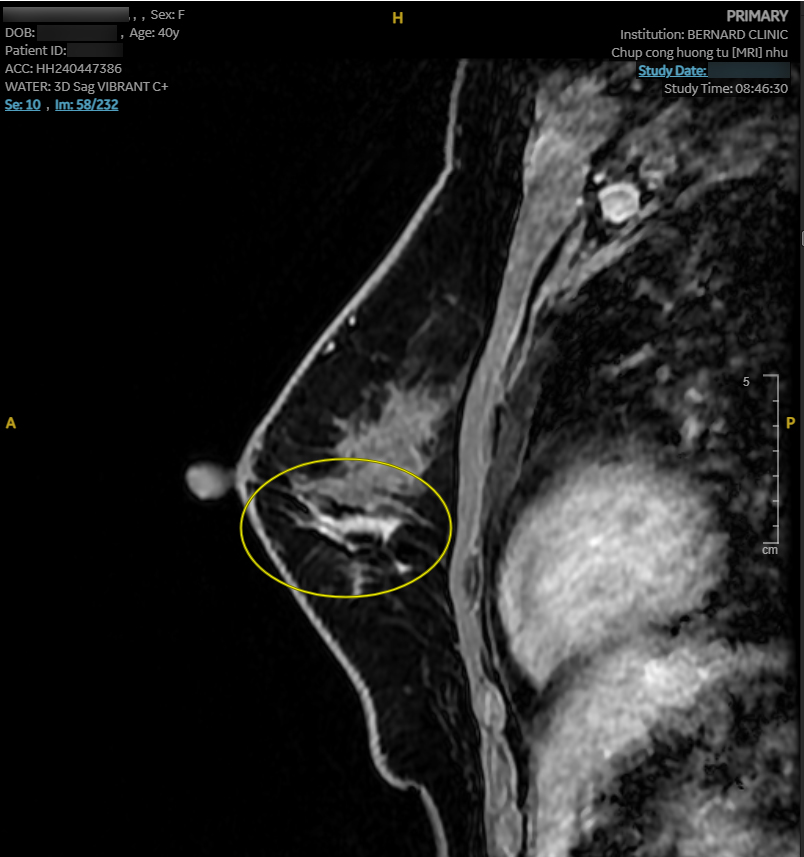

Hình ảnh MRI cho thấy nhiều bất thường. Vú phải có nang vú vị trí 6 giờ, cách núm vú 3cm, d-7mm, phân loại BI-RADS 2. Vú trái có bất thường tín hiệu diện rộng 1/2 dưới (6 - 8 giờ), giới hạn bờ kém rõ, tổn thương dạng đám/nốt/đường, BI-RADS 4.

Nhận thấy hình ảnh MRI bất thường, Hội đồng Y khoa Bernard lập tức chuyển hội chẩn “second opinion” với các Giáo sư Chẩn đoán hình ảnh của Bệnh viện Đại học Yamanashi (Nhật Bản). Kết luận từ chuyên gia Nhật tương đồng: tổn thương trong ống tuyến - nghi ung thư tại chỗ (carcinoma in situ), BI-RADS 4B.